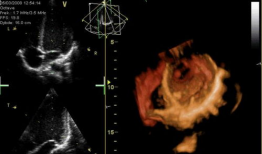

心脏跳动的视频,揭秘心脏跳动的奥秘

你知道吗?最近在网上流传着一个特别神奇的视频,它记录了心脏跳动的瞬间。这可不是普通的视频,它让我们仿佛能感受到心跳的力量,那种感...